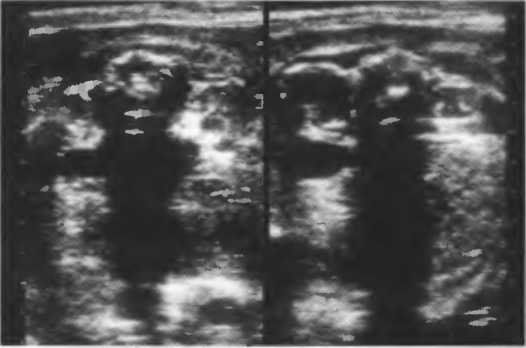

Рис.5. Два поперечных среза плода, демонстрирующих тень от позвоночника плода. Аналогичная тень от ребер может частично закрывать почки или печень. Изменяя угол наклона датчика, можно изменить положение тени таким образом, чтобы подлежащие ткани были видны отчетливо.

Кости, камни и кальцинаты дают акустическую тень. Ультразвук не может проходить через кость, если она только не очень тонкая (как, например, кости черепа у новорожденного). При необходимости рассмотреть структуры, расположенные глубже, необходимо использовать различные углы наклона датчика (рис. 17а,б).

Рис. 176. Это изображение почки частично экранировано тенью ребра. Сканирование в различные фазы дыхания поможет визуализировать всю почку целиком, «вывести» ее из-под ребра.